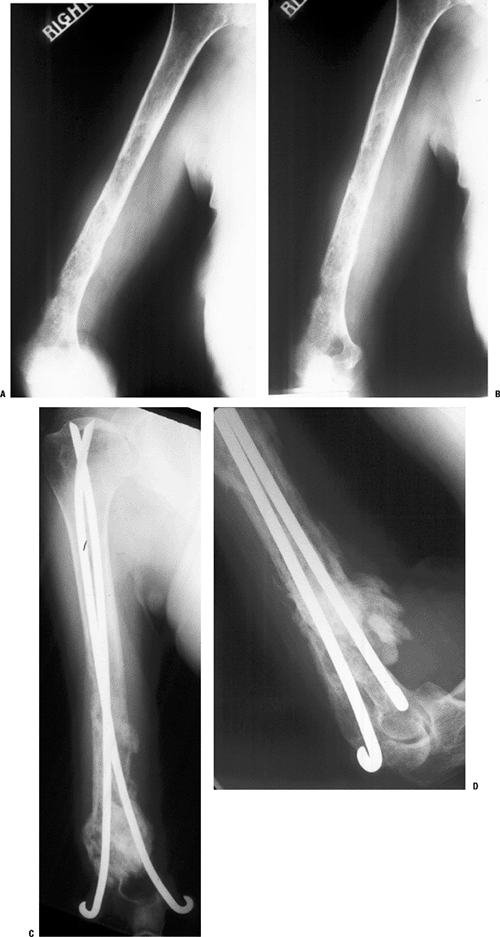

Figure 4.5-11 A patient with metastatic breast carcinoma involving much of the humerus with an impending distal third fracture (A,B) was treated with dual cemented Rush rod fixation, with good results (C,D).